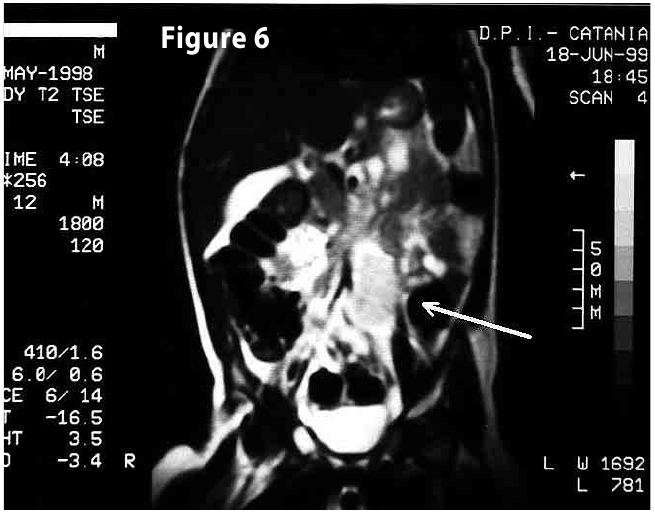

Complete objective response of neuroblastoma to biological treatment.

Figure6